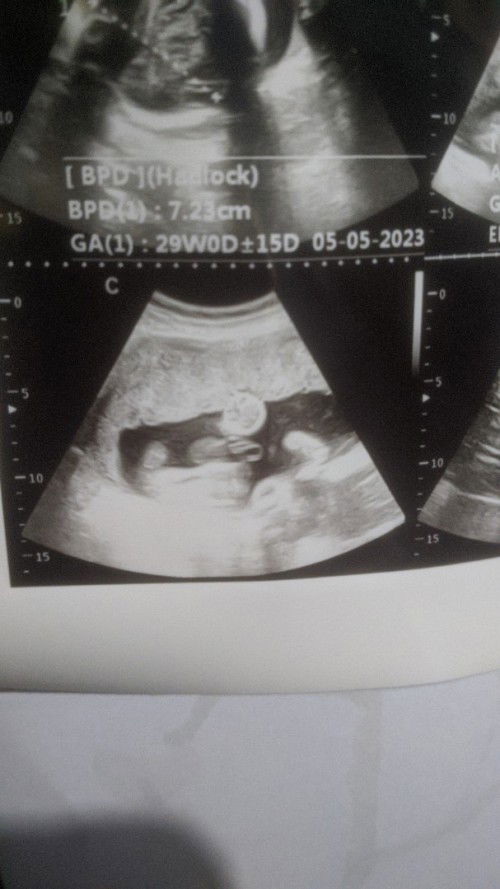

Bun sharing dong,ini aku bimbang bgt aku punya BPJS tpi d faskes yg tertera g ada dr.spog/GK melayani persalinan, jadi selama ini aku kontrol ke puskesmas,tdi aku tanya" tentang BPJS ,nah puskesmas menyarankan pindah faskes ke puskesmas aja, pindah faskes emang bisa dan gampang tpi GK bisa lagsg d gunakan hrus nunggu 1bln,sdgkan hpl ku 10mei takut nya sblm BPJS aktif udh kontraksi, aku bingung bunda, Dani apa ada yg kya aku faskes 1 tidak melayani persalinan tpi ingin menggukan BPJS ketika melahirkan caranya gmna #bantusharing